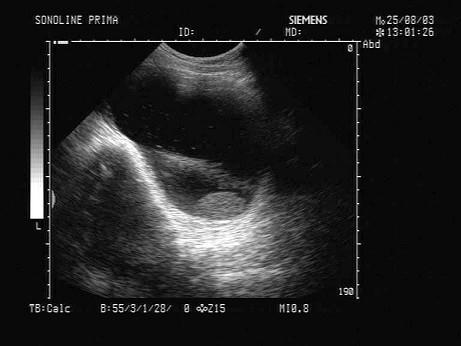

问题 女,34岁,B超检查,盆腔内可见一肿块,声像图如下,最可能的诊断为?(?)

选项 A.巧克力囊肿 B.畸胎瘤 C.炎性包块 D.宫外孕 E.附件囊肿

答案 B